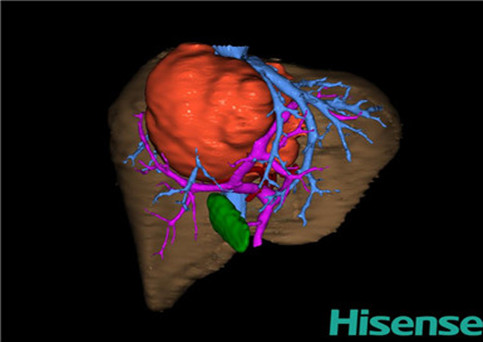

目前常用的检查方法有B超检查、CT、MRI、血管造影等。与其它的腹部肿块的诊断不同,对于小儿肝母细胞瘤血管造影具有重要的意义,可以作为手术前介入治疗的手段,也可为手术提供非常有效的影像学指导,但技术要求高,操作较复杂,且给患儿带来一定的痛苦。近年借助计算机辅助手术系统进行CT原始影像三维重建、手术规划和计算机虚拟手术技术,为精准肝脏手术提供了极为有效的技术支持。

近年来由于数字医学的发展,基于可视化三维重建技术的计算机辅助手术系统极大推进了小儿肝脏肿瘤的精准手术的进步。可以立体透视肝脏解剖、精确掌握肝段的边界、精确测算肝段乃至任意血管所支配的功能体积、准确定位病灶及其与邻近血管的解剖关系,最终对不同手术方案进行比较、筛选和优化。因此,计算机辅助手术规划系统是实现精准肝切除的有力辅助工具,是未来数字外科、精准外科等21世纪外科新理念的重要技术支撑。

计算机辅助手术规划系统具有良好的操作可行性、计算准确性和三维显示效果,可半透明、交互式显示真实的肝内立体解剖关系和空间管道变异,准确计算肝内管道的直径、走行角度,两点间的垂直距离,和任意血管的支配或引流范围等传统二维影像无法获取的信息,有助于实施个体化手术,提高了手术的确定性、预见性和可控性。计算机辅助手术规划系统可直观显示预留肝脏的结构和功能,并可通过虚拟切割功能辅助术者对手术方案进行蹄选和优化,系统评估手术风险和制定对策,改变了部分二维规划的术式和切除范围,使部分二维规划认为不能切除的患者成功手术,提高了手术的根治性、安全性和病变的可切除性,更加符合精准肝脏外科的术前规划要求。详见第11章。

随着计算机技术及影像检查技术的不断发展,以精确的术前影像学和功能评估、精细的手术操作为核心的精准肝切除技术日益受到重视。基于数字医学的计算机辅助手术技术(computer-assisted surgery,CAS)则是实现肝脏精准手术操作的基础。计算机辅助手术系统(CAS)可将术前二维(two dimensional,2D)的CT/MRI影像数据进行三维(three dimensional,3D)重建,建立个体化的肝脏三维解剖模型,清晰显示肝脏内脉管系统的走行及解剖关系,还原病灶与其周围脉管结构的立体解剖构象,准确地对病变进行定位、定性和评估,制定合理、定量的手术方案,实施个体化的肝脏血管取舍分配方案及实施精准肝脏手术。一般认为CAS包括:创建虚拟的患者的图像;患者图像的分析与深度处理;诊断、手术前规划、手术步骤的模拟;术中实时导航。应用本技术后,由于可以更清晰地看出肿瘤的界限,特别是根据肝血管的显影,判断出肿瘤与门静脉及肝静脉的关系以在手术前较准确地估计出手术成功切除的可行性。以往部分根据普通强化CT判断无法手术的病例而被评估为可以成功切除并手术成功。